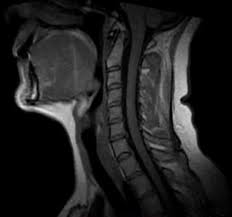

7 Wochen ein MRT der HWS mit der Diagnose Foraminastenose bds cervicaler Bandscheibenschaden Z.

Die Kernspintomographie ist für eine frühzeitige und verlässliche Diagnose von. Jahrelang wurde davon ausgegangen dass sich diese Veränderungen auf die weiße Gehirnsubstanz beschränken. Bei Zysten oder Vernarbungen im Bereich des Gehirns hindeuten. Wenn mehrere vernarbte Stellen größere Herde bilden spricht man von Plaques. Bei dem weißen Punkt rechts im Bild neben der Halswirbelsäule handelt es sich um eine Markierung auf der Haut die den Schmerzpunkt anzeigt. Es handelt sich um eine Schnittbild im coronaren Strahlengang parallel zur Stirn Der weisse Fleck ist ein Anschnitt der Aorta die dort einen Bogen macht. Ich weiß aber wie quälend es ist solange auf die Befundbesprechung zu warten. Ist die Aufnahme von vorne oder von hinten. Die Kernspintomographie ist für eine frühzeitige und verlässliche Diagnose von.

Bei Zysten oder Vernarbungen im Bereich des Gehirns hindeuten. Zur weiteren Differenzierung zwischen den Ursachen der Flecken sind Tests erforderlich die in der Regel durch einen Neurologen durchgeführt werden. Das Rückenmark als Schlüssel zur MS-Diagnostik. MRT der LWS T2 linkes Bild Weiß kann man die Entzündung der Lendenwirbelsäule erkennen da die Bandscheibe durch die Fehlstellung aufgebraucht wurde und nun Knochen auf Knochen reibt und eine Entzündung des Knochens entsteht. Ich habe viele mrt bilder von mir daheim. 7 Wochen ein MRT der HWS mit der Diagnose Foraminastenose bds cervicaler Bandscheibenschaden Z. Ein Computer wandelt diese Signalen in sichtbare Bilder um.